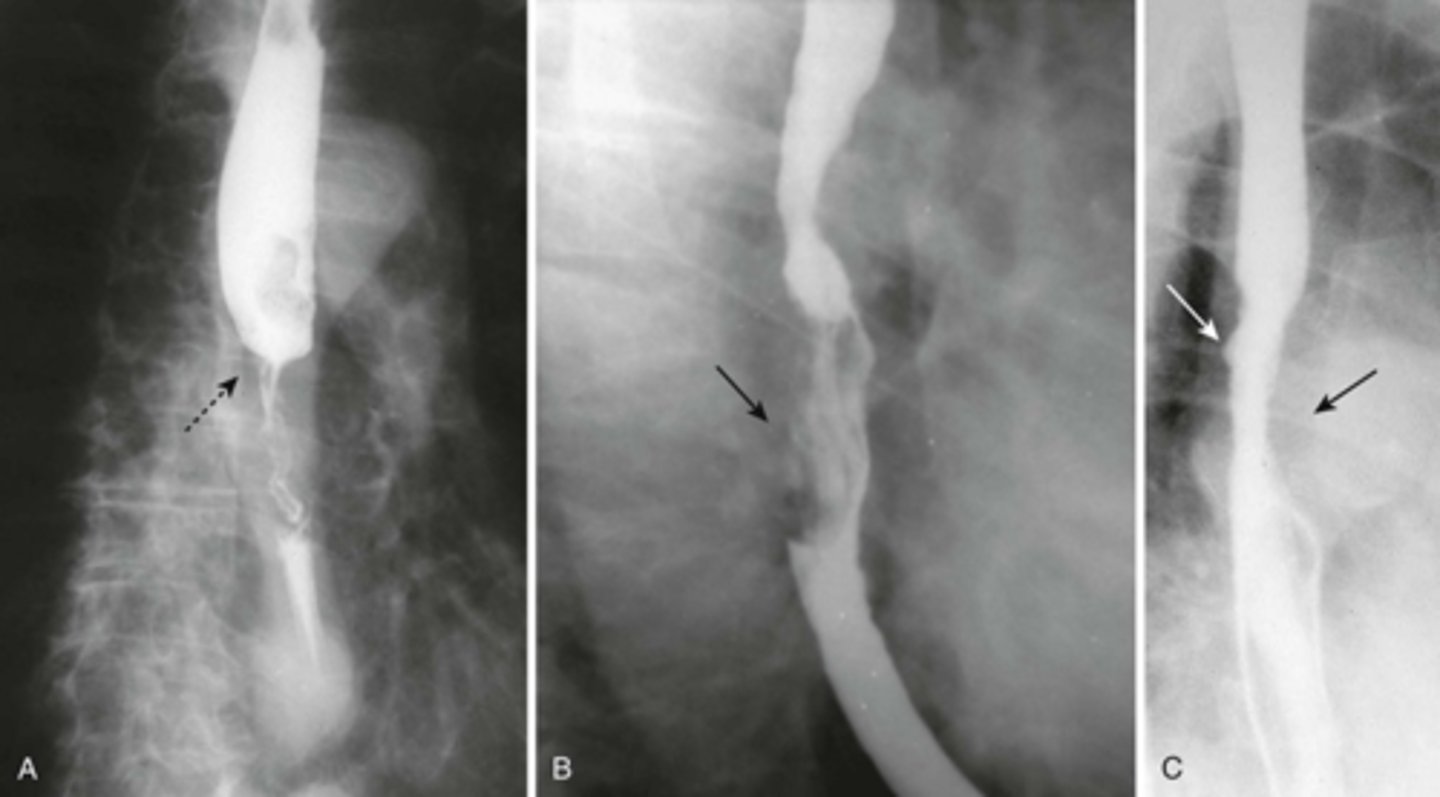

Esophageal diverticula.

(A)WHITE ARROW:

localized weakness in the posterior wall of the hypopharynx;

in the mid-esophagus from extrinsic disease such as tuberculosis that causes fibrosis, which pulls on the esophagus, forming a traction diverticulum (dotted white arrow)

DOTTED WHITE ARROW:

traction diverticulum. fibrosis pulling on the esophagus.

B: BLACK ARROW:

Epiphrenic diverticulum, just above the diaphgram in the distal esophagus.

(C). Only the traction diverticulum is a true diverticulum in that it has all layers of the esophagus involved; the Zenker and epiphrenic are false or pseudodiverticula because the mucosa and submucosa herniate through a defect in the muscular layer. The Zenker diverticulum is the only one of the three that typically produces symptoms.

Esophageal carcinomas.

(A)

DOTTED BLACK ARROW:

annular constricting lesion of the midesophagus.

The tumor encircles the normal lumen and obstructs it in this case.

(B)

BLACK ARROW: Polypoid mass that arises from the right lateral wall of the esophagus and displaces the barium around it.

(C)

BLACK ARROW - wall, irregular and rigid

WHITE ARROW: a small ulceration (white arrow).